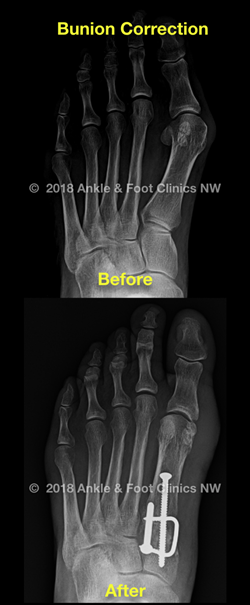

Bunions are progressive foot deformities involving the big toe and adjacent first metatarsal bone. When the condition causes chronic inflammation, irritation and pain, surgical correction is often necessary. Surgical removal of a bunion is referred to as bunionectomy. However bunionectomy rarely involves simple bump removal due to the complex nature of the condition.

Bunion surgeries fall into two major categories:

• Head procedures that treat the big toe joint. In a head procedure bunionectomy, the bone is bud behind the joint, moved into its proper position, and fixed in place with a screw or pin. Head procedures are often used for patients who cannot be immobilized for long periods of time.

• Base procedures concentrate on the bone near or behind the big toe joint. Different types of base procedures are conducted depending on the nature of the deformity. These range from cutting a wedge out of the bone, placing a curved cut, or fusing the base joint. All procedures involve reduction of the deformed part into a more corrected position.